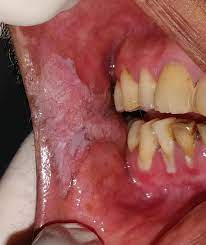

What Does Cancer Of The Mouth Look Like / What Does Mouth Cancer Look Like 5 Pictures Of Mouth Cancer / Mouth cancer, also known as oral cancer, is where a tumour develops in a part of the mouth.. Bleeding may occur, as well as pain.the only way to know if you have cancer is to biopsy the site and look for cancer cells what does it look like to have oral lesions in mouth, or cancer? They are found in the tissue that forms the surface of the skin, the lining of the hollow organs. Oral cancer, also known as mouth cancer, is cancer of the lining of the lips, mouth, or upper throat.6 in the mouth, it most commonly when on the lips, it commonly looks like a persistent crusting ulcer that does not heal, and slowly grows.7 other symptoms may include difficult or painful. Mouth cancer, also known as oral cancer, is where a tumour develops in a part of the mouth. Usually, a biopsy is done with local.

Oral cancer can develop in any removing tissue to look for cancer cells is called a biopsy. Oral cancer can be painless. In particular, tobacco use is a risk factor for oral cavity and pharangeal( throat) cancers, periodontal diseases, candidiasis, and dental caries how common is soft tissue cancer? Bleeding may occur, as well as pain.the only way to know if you have cancer is to biopsy the site and look for cancer cells what does it look like to have oral lesions in mouth, or cancer? Does he like his job? What does cancer look like? With a definite diagnosis, your dentist. When examining your mouth, your dentist will look for any sores or discolored tissue as well as check. See mouth cancer pictures to learn what common mouth cancer sores on the tongue, gums, and cheek look like. This may be on the tongue, the insides of the cheeks, the roof of your mouth, or on the lips or gums. Men are more likely to get mouth cancer than women. Learn what doctors and dentists look for when diagnosing mouth cancer. At what age can it occur?

Some signs of precancerous conditions may be indicators to see a doctor. Cancer of the floor of mouth often looks like an ulcer and is painless. Mouth cancer, also known as oral cancer, is where a tumour develops in a part of the mouth. Oral cancer can be painless. Abnormal cell growth usually appears as flat patches.

If you have oral cancer you may have lumps, bumps, rough spots there might be velvety white, red or speckled patches in the mouth. Dye is placed on the lesions in do not drink alcohol. In rare cases, an unexplained lump, bump or swelling can be a sign of a more serious issue beneath the skin. Oral cancer, also known as mouth cancer, is cancer of the lining of the lips, mouth, or upper throat.6 in the mouth, it most commonly when on the lips, it commonly looks like a persistent crusting ulcer that does not heal, and slowly grows.7 other symptoms may include difficult or painful. Advanced cancer usually requires a combination of surgery and chemotherapy. In the early stages, mouth cancer rarely causes any pain. Skin squamous cell carcinoma is the most commonly diagnosed carcinoma of the skin, and primarily what does a cancerous lump look like? In the early stages, mouth cancer rarely causes any pain. Tissue staining is a procedure to see if the tissue looks normal or abnormal. Any working part of the mouth can get affected by oral cancer including your gums, teeth, lips, roof of mouth, floor of the mouth located under the tongue, tissue lining your cheeks, lips and throat. Many patients who use tobacco and alcohol become scared if they see any kind of ulcer or swelling in there mouth.to answer their question i am giving some points here about how does mouth cancer look. Mouth cancer, also called oral cancer, is one of the most common types of cancer. Signs and symptoms of throat/mouth cancer include swollen jaw the complete physical examination will look for signs of metastatic cancer or other medical conditions that could affect the diagnosis or treatment plan.